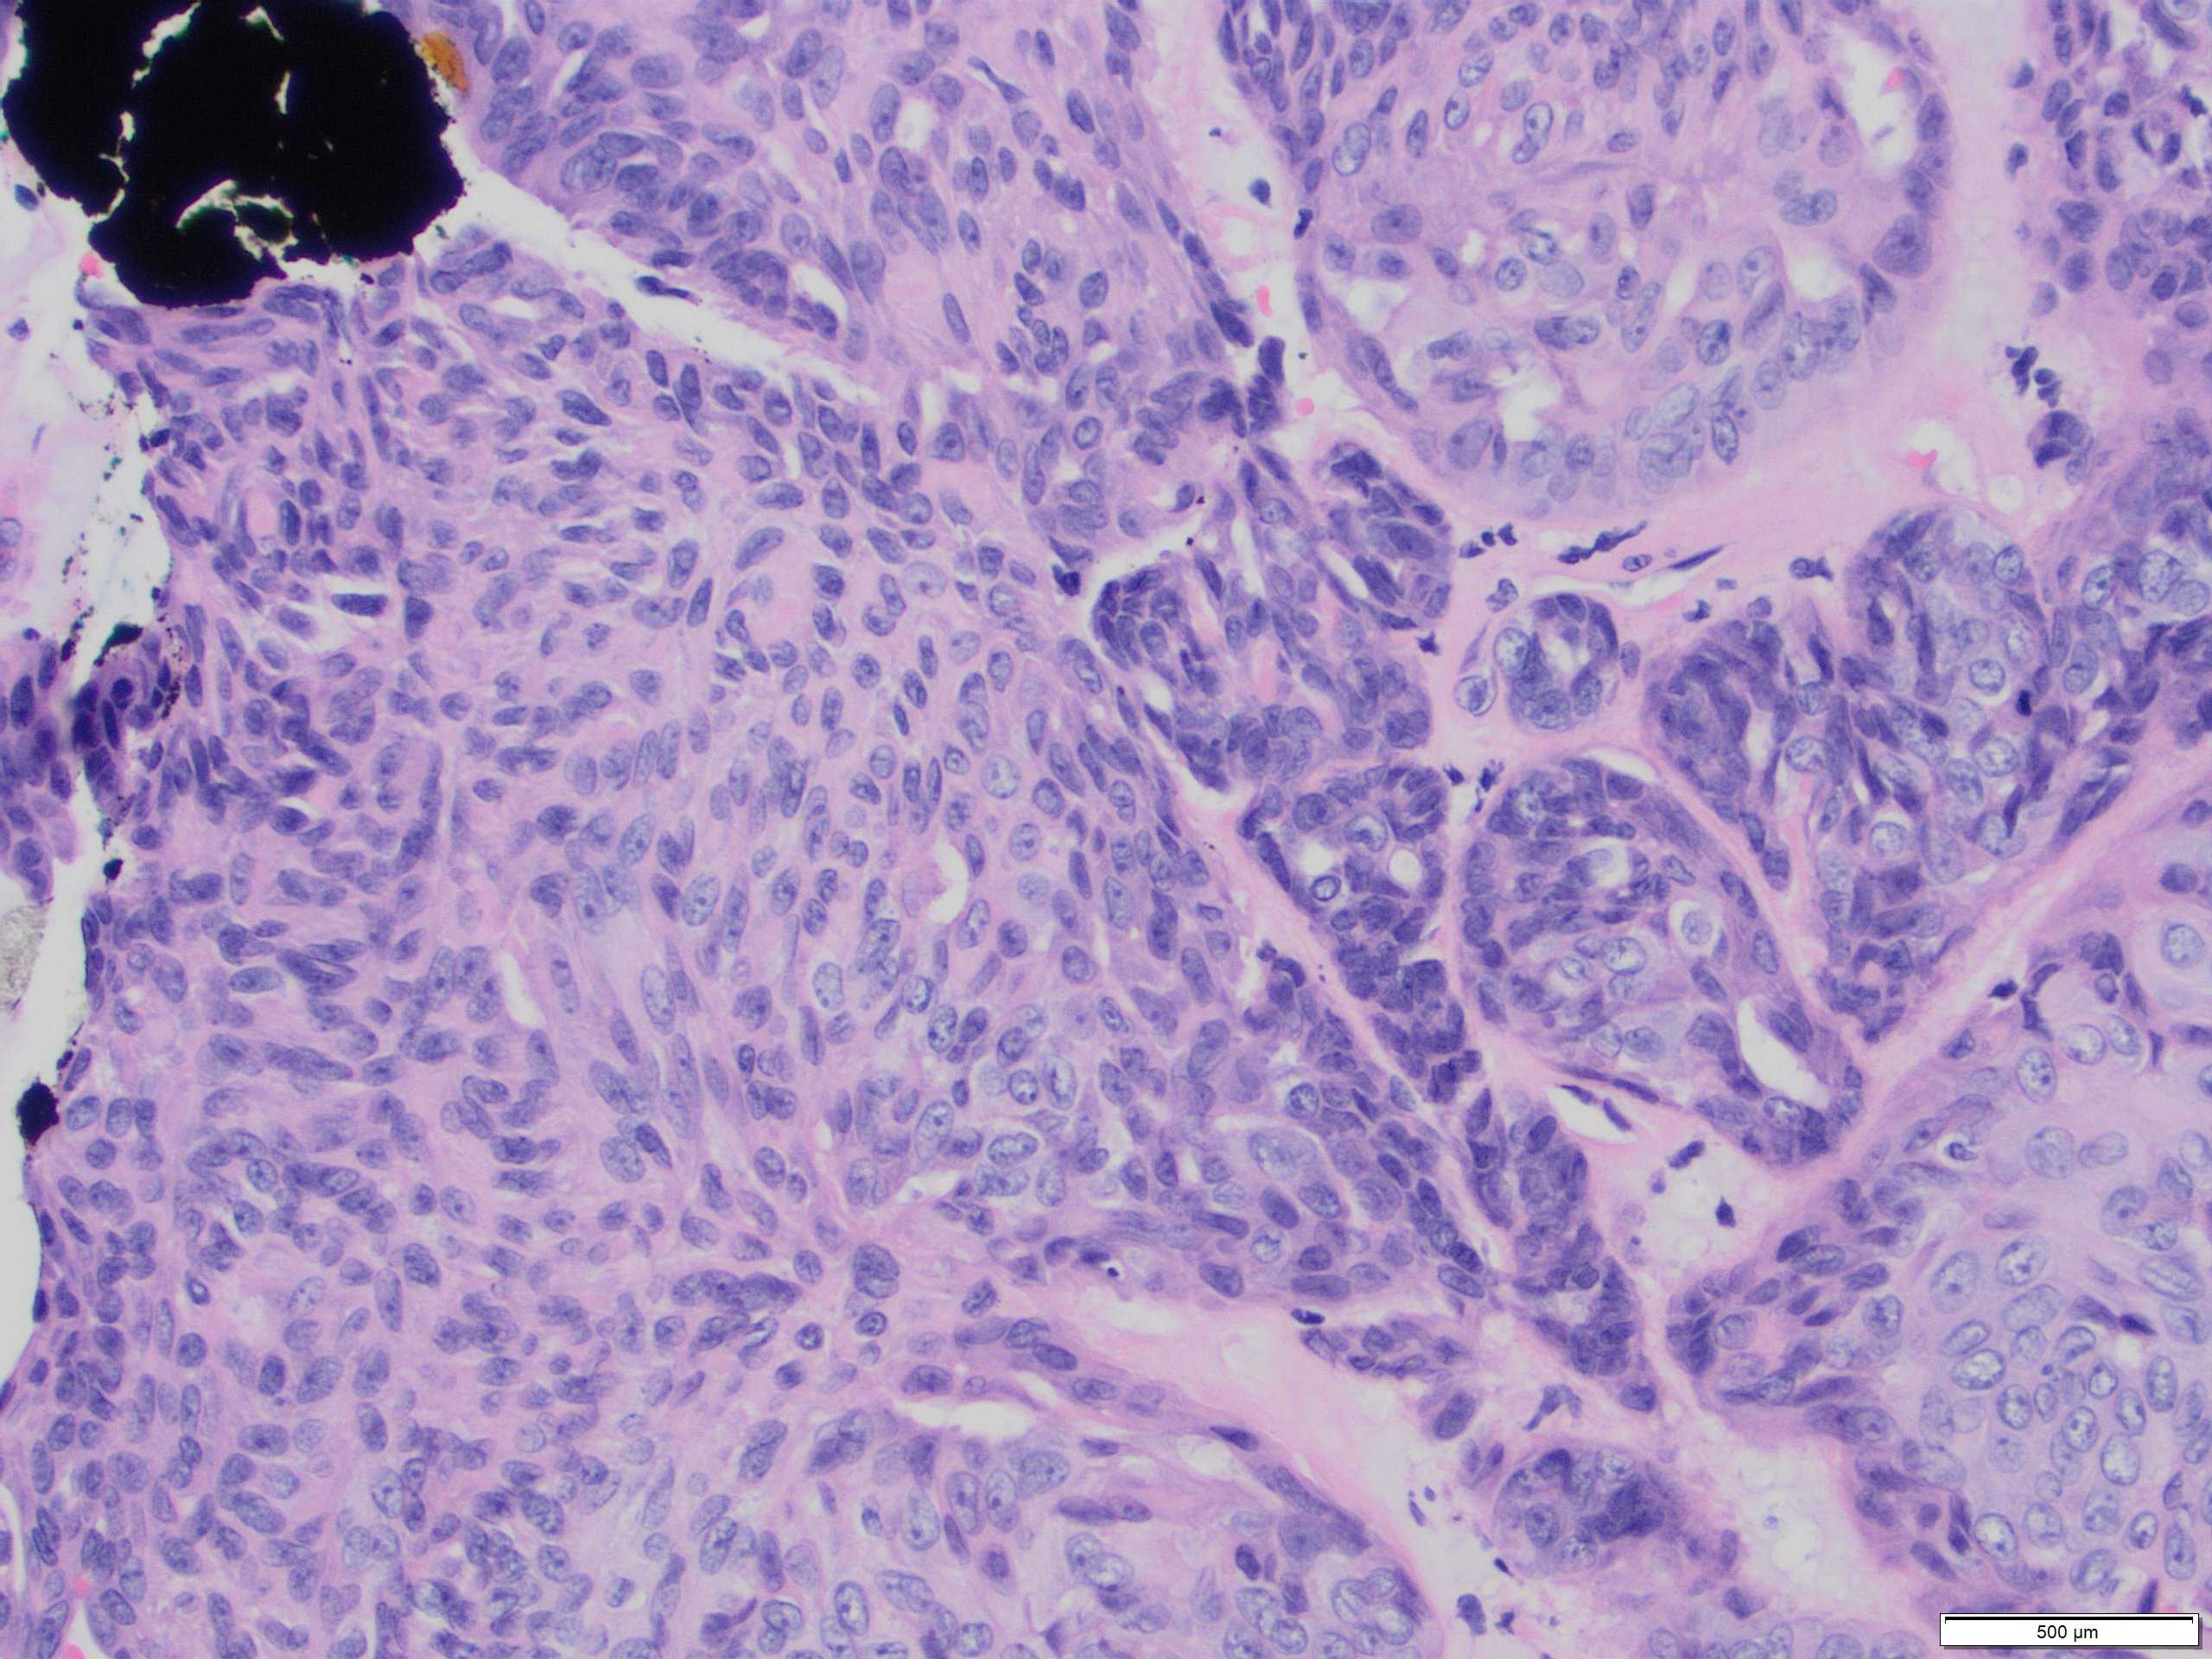

Classical benign AME comprises epithelial and myepithelial (MECs) with varying ratios within and between tumours. MECs usually dominate and are more numerous than the single basal layer component of the epithelial myoepithelial bilayer of normal breast lobules, adenosis nodules or simple papillomas. The cells are often small and uniform without cytological atypia or increased mitotic activity.

Malignant AME (M-AME) shows varied macroscopic appearances from a multilobulated, well-defined mass, similar to classic AME, to a poorly defined mass with infiltrative borders. Histological features of malignancy: overgrowth of the epithelial or myoepithelial component, mild to moderate cytological atypia, and increased mitotic activity with or without mildly infiltrative growth pattern, and/or focal necrosis.

M-AME may show an aberrant immunoprofile with loss of distinction of the dual cell population. The epithelial cell component may be positive for ER and EMA/MUC1 and show strong E-cadherin membrane expression. Complete absence of hormone receptor expression has been reported in 40% of AMEs, associated with nuclear atypia, necrosis and/or increased mitotic activity. HER2 is usually negative in these tumours.